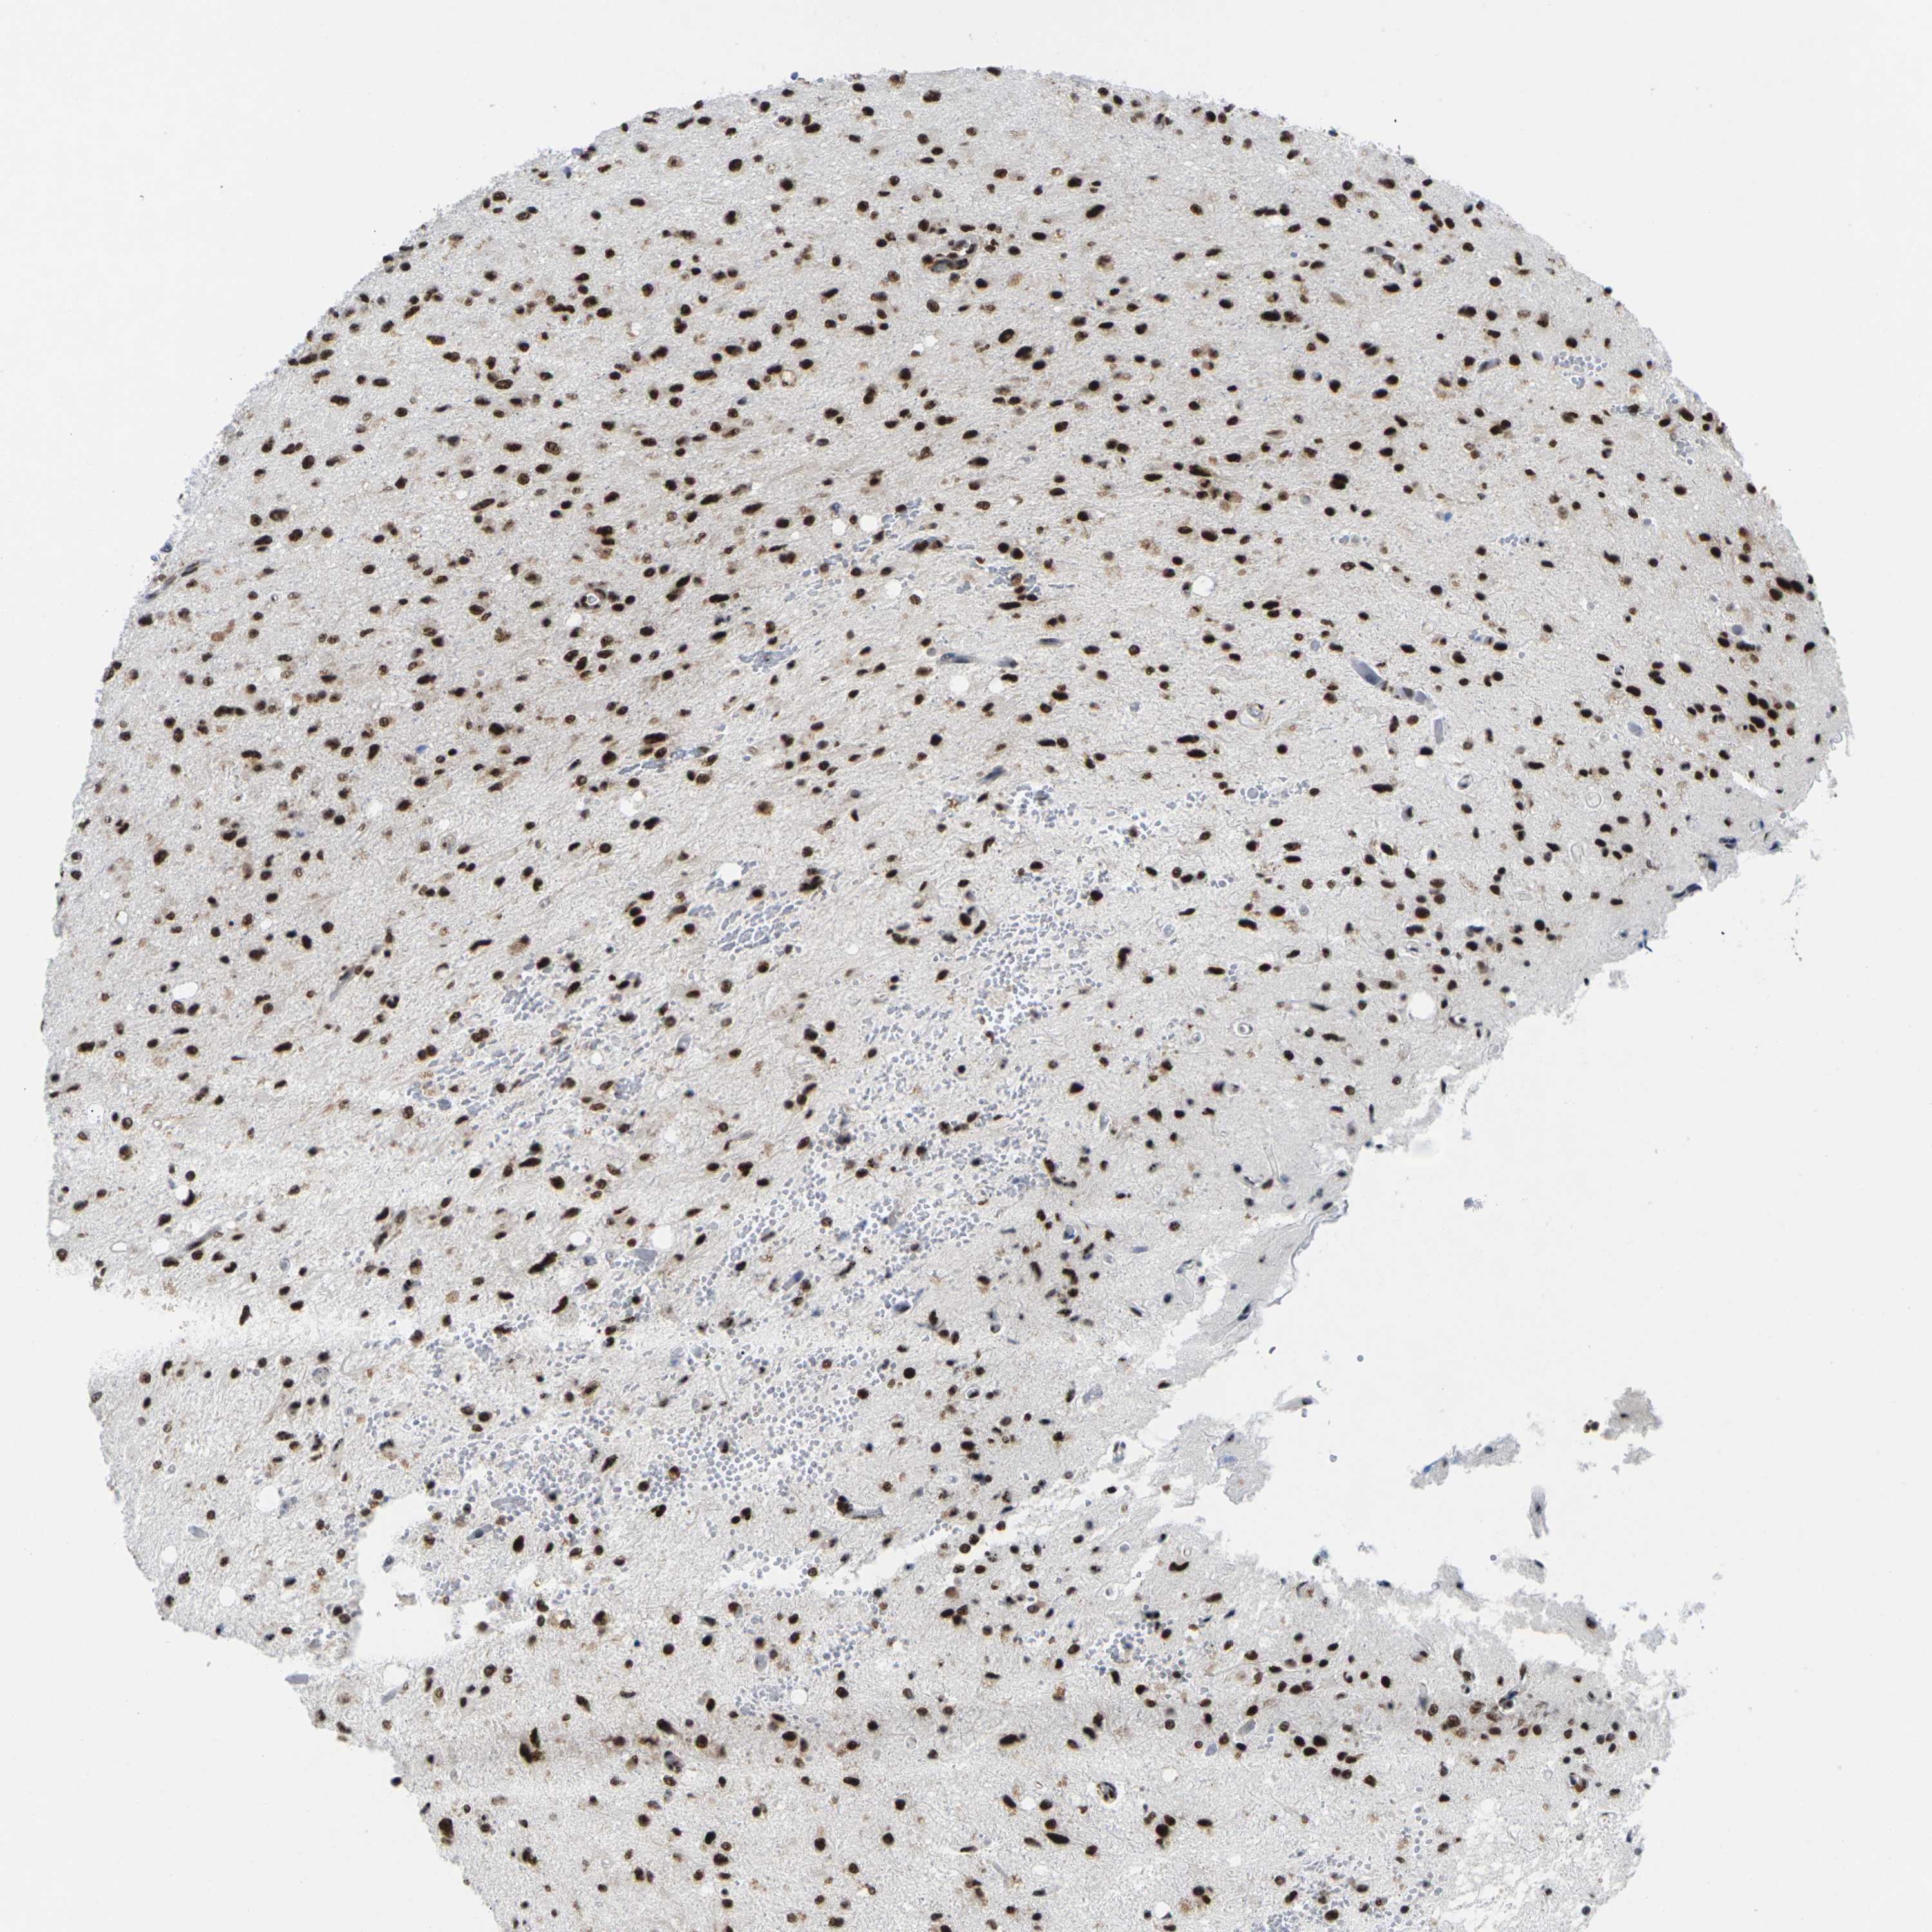

GLIOMA - Protein expressioni

A mouse-over function shows sample information and annotation data. Click on an image to view it in a full screen mode. Samples can be filtered based on level of antibody staining by selecting one or several of the following categories: high, medium, low and not detected. The assay and annotation is described here.

Note that samples used for immunohistochemistry by the Human Protein Atlas do not correspond to samples in the TCGA dataset.

Antibody stainingi

Antibody staining in the annotated cell types in the current human tissue is reported as not detected, low, medium, or high, based on conventional immunohistochemistry profiling in selected tissues. This score is based on the combination of the staining intensity and fraction of stained cells.

Each image is clickable and will lead to virtual microscopy that enables deeper exploration of all samples and also displays staining intensity scores, fraction scores and subcellular localization as well as patient and tissue information for each sample.

Antibody HPA043036

Antibody HPA047754

Antibody CAB015425

Staining

High

Medium

Low

Not detected

Intensity

Strong

Moderate

Weak

Negative

Quantity

>75%

75%-25%

<25%

None

Location

Nuclear

Cytoplasmic/membranous

Cytoplasmic/membranous,nuclear

Glioma, malignant, High grade

Glioma, malignant, Low grade

Glioma, malignant, NOS